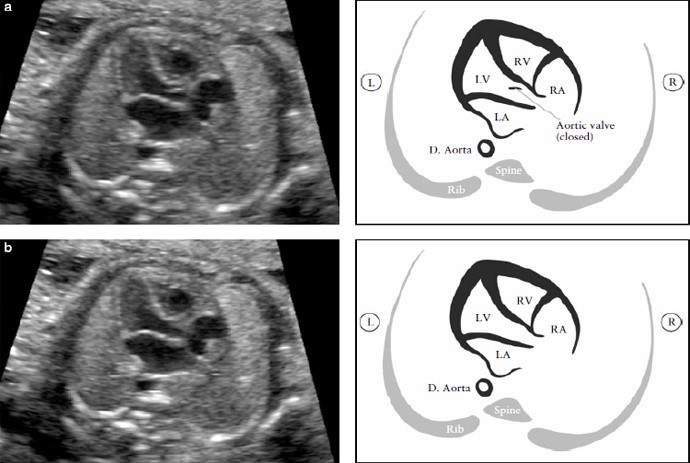

В этом срезе необходимо тщательно оценить специфические критерии и не следует ограничиваться простым подсчетом камер сердца. Основные элементы, которые необходимо оценить в этом срезе представлены в таблице 1 и на рисунках 1 и 2. Для оценки позиции сердца необходимо сначала определить положение плода, то есть идентифицировать его правую и левую стороны, а потом определить левостороннее расположение желудка и сердца плода.

Рисунок 1. (А) Поперечный срез живота плода: определение ситуса. После определения положения плода в утробе матери необходимо идентифицировать желудок плода в левой стороне живота; там же, где видна нисходящая аорта (D. Aorta) – слева, и нижняя полая вена (IVC) – справа от позвоночника. Короткий сегмент пупочной вены (UV) также должен визуализироваться. (b) Направление оси сердца: сердце большей частью должно находиться в левой половине грудной клетки.

Верхушка сердца должна быть 45º по отношению к передне-задней оси грудной клетки. LA- левое предсердие, LV- левый желудочек; R- право; RA- правое предсердие; RV-правый желудочек.

Рисунок 2. Четырех-камерный срез сердца. Ключевые элементы этого среза во втором триместре: сердце занимает не более 1/3 грудной клетки, правые и левые отделы сердца почти одинаковые по размеру (размер камер и толщина стенок), клапан овального окна открывается в левое предсердие, интактный ” крест” сердца с нормальным смещением двух атриовентрикулярных клапанов и интактная межжелудочковая перегородка.

Морфологически правый желудочек идентифицируется наличием модераторного пучка и трикуспидальным клапаном, который располагается более апикально по отношению к митральному клапану. D. Aorta- нисходящая аорта ; L- левый; LV-левый желудочек; R- правый; RA- правое предсердие

Рисунок 5. Выходной тракт левого желудочка (LVOT). Этот срез демонстрирует соединение сосуда с левым желудочком (LV). Крайне важно увидеть отношение между межжелудочковой перегородкой и передней стенкой этого сосуда, который в норме является аортой. Аортальный клапан не должен быть утолщен и должен свободно открываться. Аортальный клапан закрыт (а) и открыт (b). D aorta- нисходящая аорта; L-левый; LA – левое предсердие; R- правый; RA-правое предсердие; RV- правый желудочек.